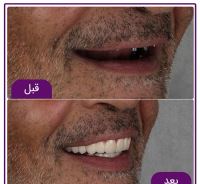

• گالری

ظاهر طبیعی: با نصب دندان مصنوعی فوری بر روی ایمپلنت، بیماران میتوانند به طور فوری از ظاهر طبیعی دندانهای خود بهرهبرده و از خنثی خوردن غذا و لبخند بهرهمند شوند.

می توان گفت ایمپلنت دندان یک روزه و ایمپلنت فوری هیچ تفاوتی ندارند و هر دو یک روش می باشند. در این روش جراح بدون هیچ خونریزی و دردی در کمترین زمان ممکن اقدام به نصب ایمپلنت و همچنین قرار دادن تاج بر روی آن می کند. دیگر نیازی نیست بیمار تا چند ماه منتظر بماند تا ایمپلنت به استخوان فک جوش بخورد. تنها در یک روز این روش برای اصلاح دندان از دست رفته انجام میگیرد.

در مرحله آخر و در روز جراحی و بلافاصله بعد از قرار دادن ایمپلنت، روکش ایمپلنت که دارای ظاهری بسیار طبیعی و زیبا می باشد، برای بیمار نصب خواهد شد. در واقع در روش ایمپلنت دیجیتال، بیمار حتی یک روز هم بدون دندان نمی ماند.